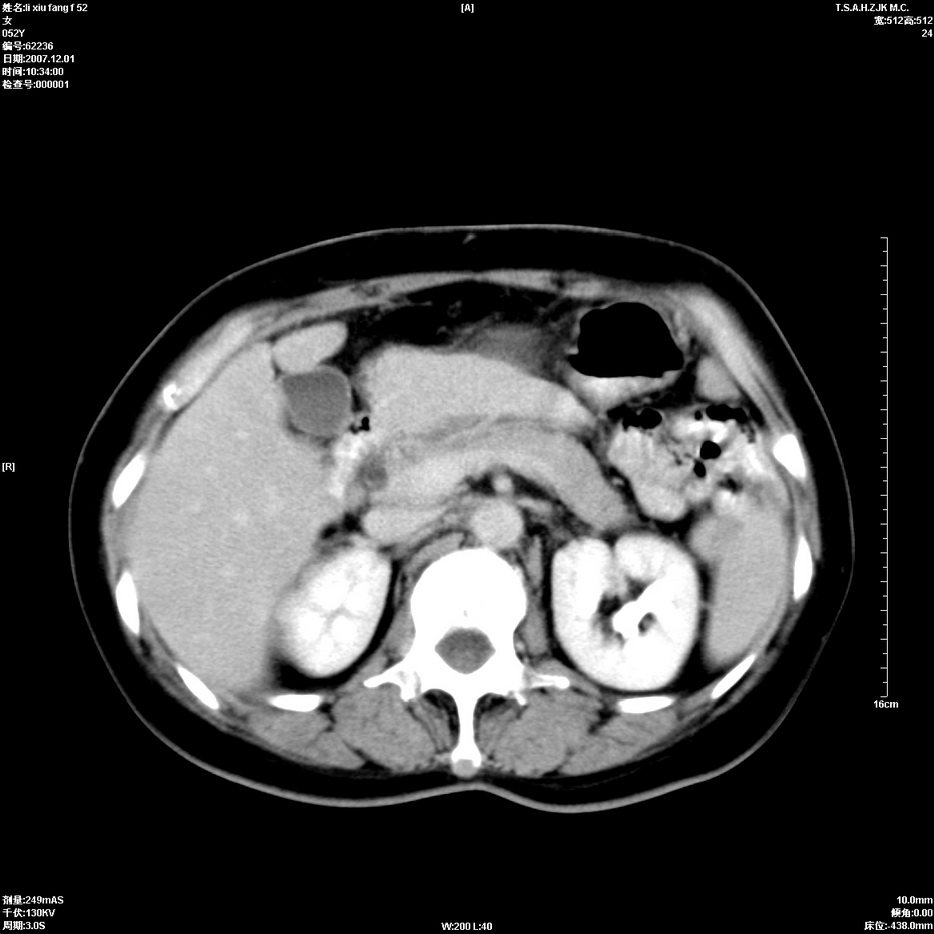

标题: CT12858:女,52岁,胎甲球蛋白861肝左叶占位,肝癌。下腔静 [打印本页]

标题: CT12858:女,52岁,胎甲球蛋白861肝左叶占位,肝癌。下腔静

肝左叶巨大低密度灶肿块,增强符合快进快出表现,有动静脉交通支;静脉期,下腔静脉内有充盈缺损,afp明显升高,支持肝癌并下腔静脉癌栓形成。

支持楼主   门静脉主干及左支癌栓形成

以下是引用拾荒者在2008-4-15 22:57:00的发言:[br]肝左叶巨大低密度灶肿块,增强符合快进快出表现,有动静脉交通支;静脉期,下腔静脉内有充盈缺损,afp明显升高,支持肝癌并下腔静脉癌栓形成。